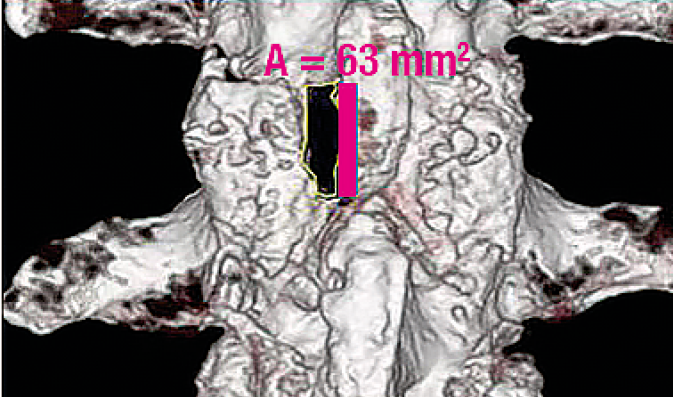

Facet joint preserving decompression of the dural sac